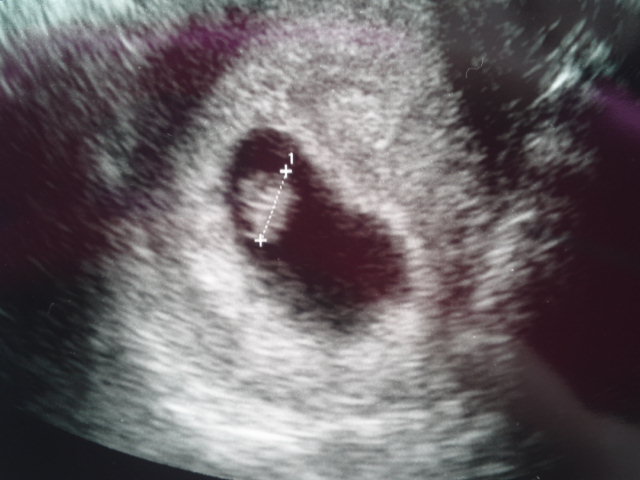

ベビちゃん授かった~♪

MRIだっけ!?

最近はかなりハッキリ見えるんだってね。